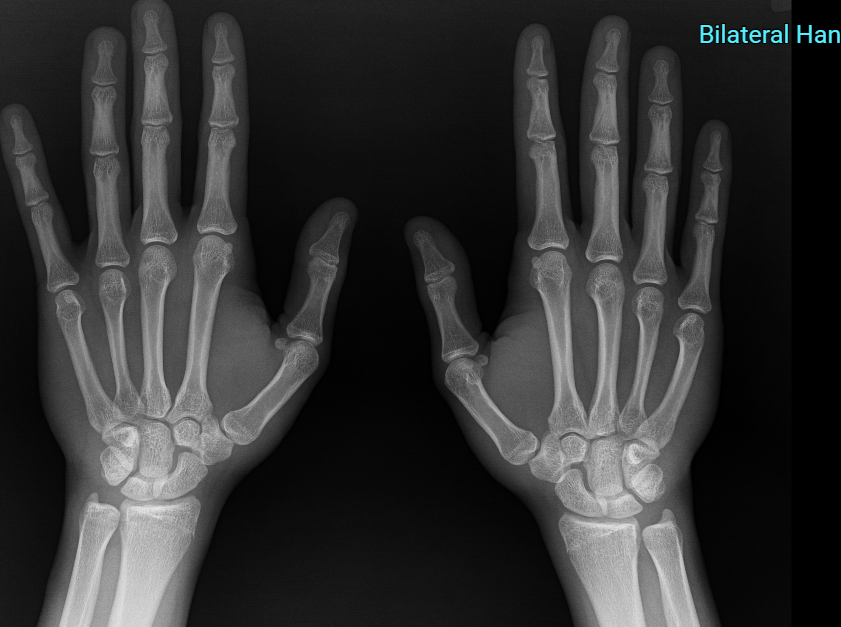

It seems they are closed in this image. Is it worth getting my femur and tibia checked.

I JUST SPENT $200 ong HGH FUCK ME.